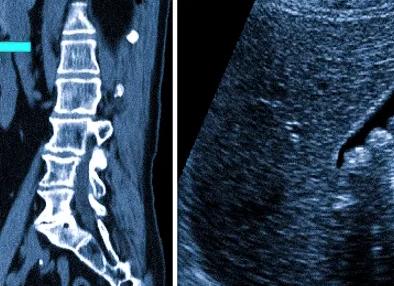

Для УЗИ применяется аппарат, который показывает состояние внутренних органов при помощи ультразвуковых волн. Проникая внутрь, такие волны отражаются от тканей и позволяют сформировать на мониторе компьютера послойное изображение обследуемой зоны, по которому врач определяет наличие или отсутствие патологий. Вся процедура обычно не занимает более 10–15 минут, и результаты можно узнать сразу.

МРТ, или магнитно-резонансная томография, представляет собой методику исследования, при которой состояние внутренних органов изучается путем получения серии их пошаговых срезов в трех плоскостях. В процессе МРТ измеряется электромагнитный отклик ядер атомов в клетках (в основном водорода) при взаимодействии с радиочастотными импульсами, которые создает постоянное магнитное поле. По причине того, что в тканях содержится неодинаковое количество водорода, на итоговых снимках можно увидеть четкую дифференциацию структуры органов брюшной полости.

Магнитно-резонансная томография с контрастом — самое безопасное и безболезненное исследование из существующих, позволяющее с высокой точностью определить целый ряд проблем с ЖКТ. Аппарат делает целый ряд снимков в разрезе, которые создают целостное представление об органе (размерах, толщине стенок, сосудах, плотности тканей и т.д.).

• томография помогает рассмотреть орган послойно в 3Д, УЗИ дает двухмерные результаты;

Магнитно-резонансная томография является более информативной, с помощью неё можно в самых мелких деталях разглядеть строение различных частей организма. При МРТ органов брюшной полости выходит очень чёткая иллюстрация состояния плотных (паренхиматозных) полых органов, просматриваются абсолютно все органы брюшной полости. В то же самое время мы получаем подробную информацию об изменениях в строении сосудистого русла, работы систем ‒ лимфатической и кровеносной.